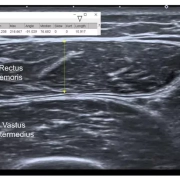

Upon examining the records, the Commission observed that it was evident that the doctors conducted proper pre-operative investigations before the surgery. The Commission emphasized the importance of pre-operative assessment to ensure the patient’s fitness for surgery, identify potential issues, and guarantee patient safety. However, the Commission agreed with the complainant’s argument that the doctors failed to conduct an MRI scan to assess the patient’s condition before the surgery. The Commission deemed the failure to perform pre-operative investigations, including an MRI scan for assessing abdominal adhesions, as gross negligence and a deficiency in service on the part of the physcians. It noted;

“We are of the view that pre-operative assessment is necessary prior to surgical procedures, in order to ensure that the patient is fit to undergo surgery, to highlight issues that the surgical or anaesthetic team need to be aware of during the peri-operative period, and to ensure patients’ safety during their journey of care. In addition, unnecessary complications due to inappropriate surgery may be avoided. In the above circumstances we find force in the contention of the complainant that the opposite parties 1 to 4 have failed to take MRI scan to assess the condition of the patient prior to performing the surgery. We are of the considered view that non-carrying out of pre-operative investigations including MRI Scan for assessing abdominal adhesions in the case in hand amount to gross negligence coupled with deficiency in service on the part of the 2nd and 3rd opposite party.”